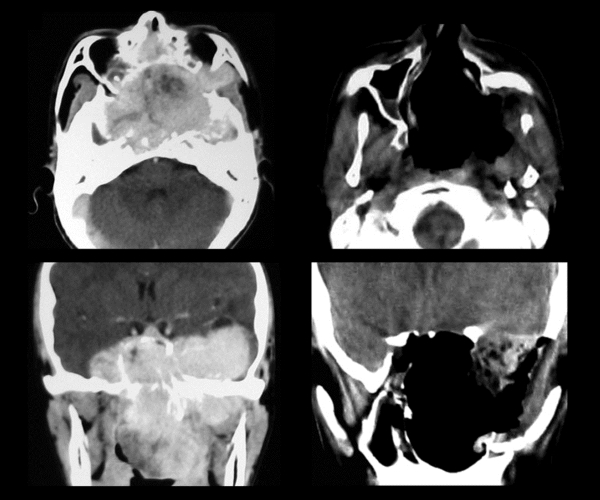

Гистологическое исследование выполняется после хирургического вмешательства для подтверждения диагноза. Если выявлена экхондрома, помимо рентгенографии и других методов, могут быть назначены магнитно-резонансная томография или компьютерная томография.

Удаление нароста в области основания черепа учитывает его расположение, влияние на окружающие ткани, наличие сопутствующих заболеваний, состояние пациента и вероятность осложнений. В некоторых случаях может потребоваться трепанация черепа или малоинвазивная операция с использованием эндоскопа, который вводится через носовой проход. Также может быть назначена лучевая терапия для уменьшения размера хрящевого новообразования перед операцией.

Часто лучевая терапия становится основным методом лечения опухолей черепа, особенно при противопоказаниях к хирургическому вмешательству. После операции может быть назначена лучевая терапия для уничтожения оставшихся раковых клеток. Стереотаксическая хирургия включает воздействие на хрящевой нарост с помощью радиационного луча. Радионож используется для удаления труднодоступных опухолей черепа и шеи, когда стандартная операция может быть рискованной из-за возможности повреждения крупных сосудов, нервной ткани или в случае тяжелого состояния пациента.